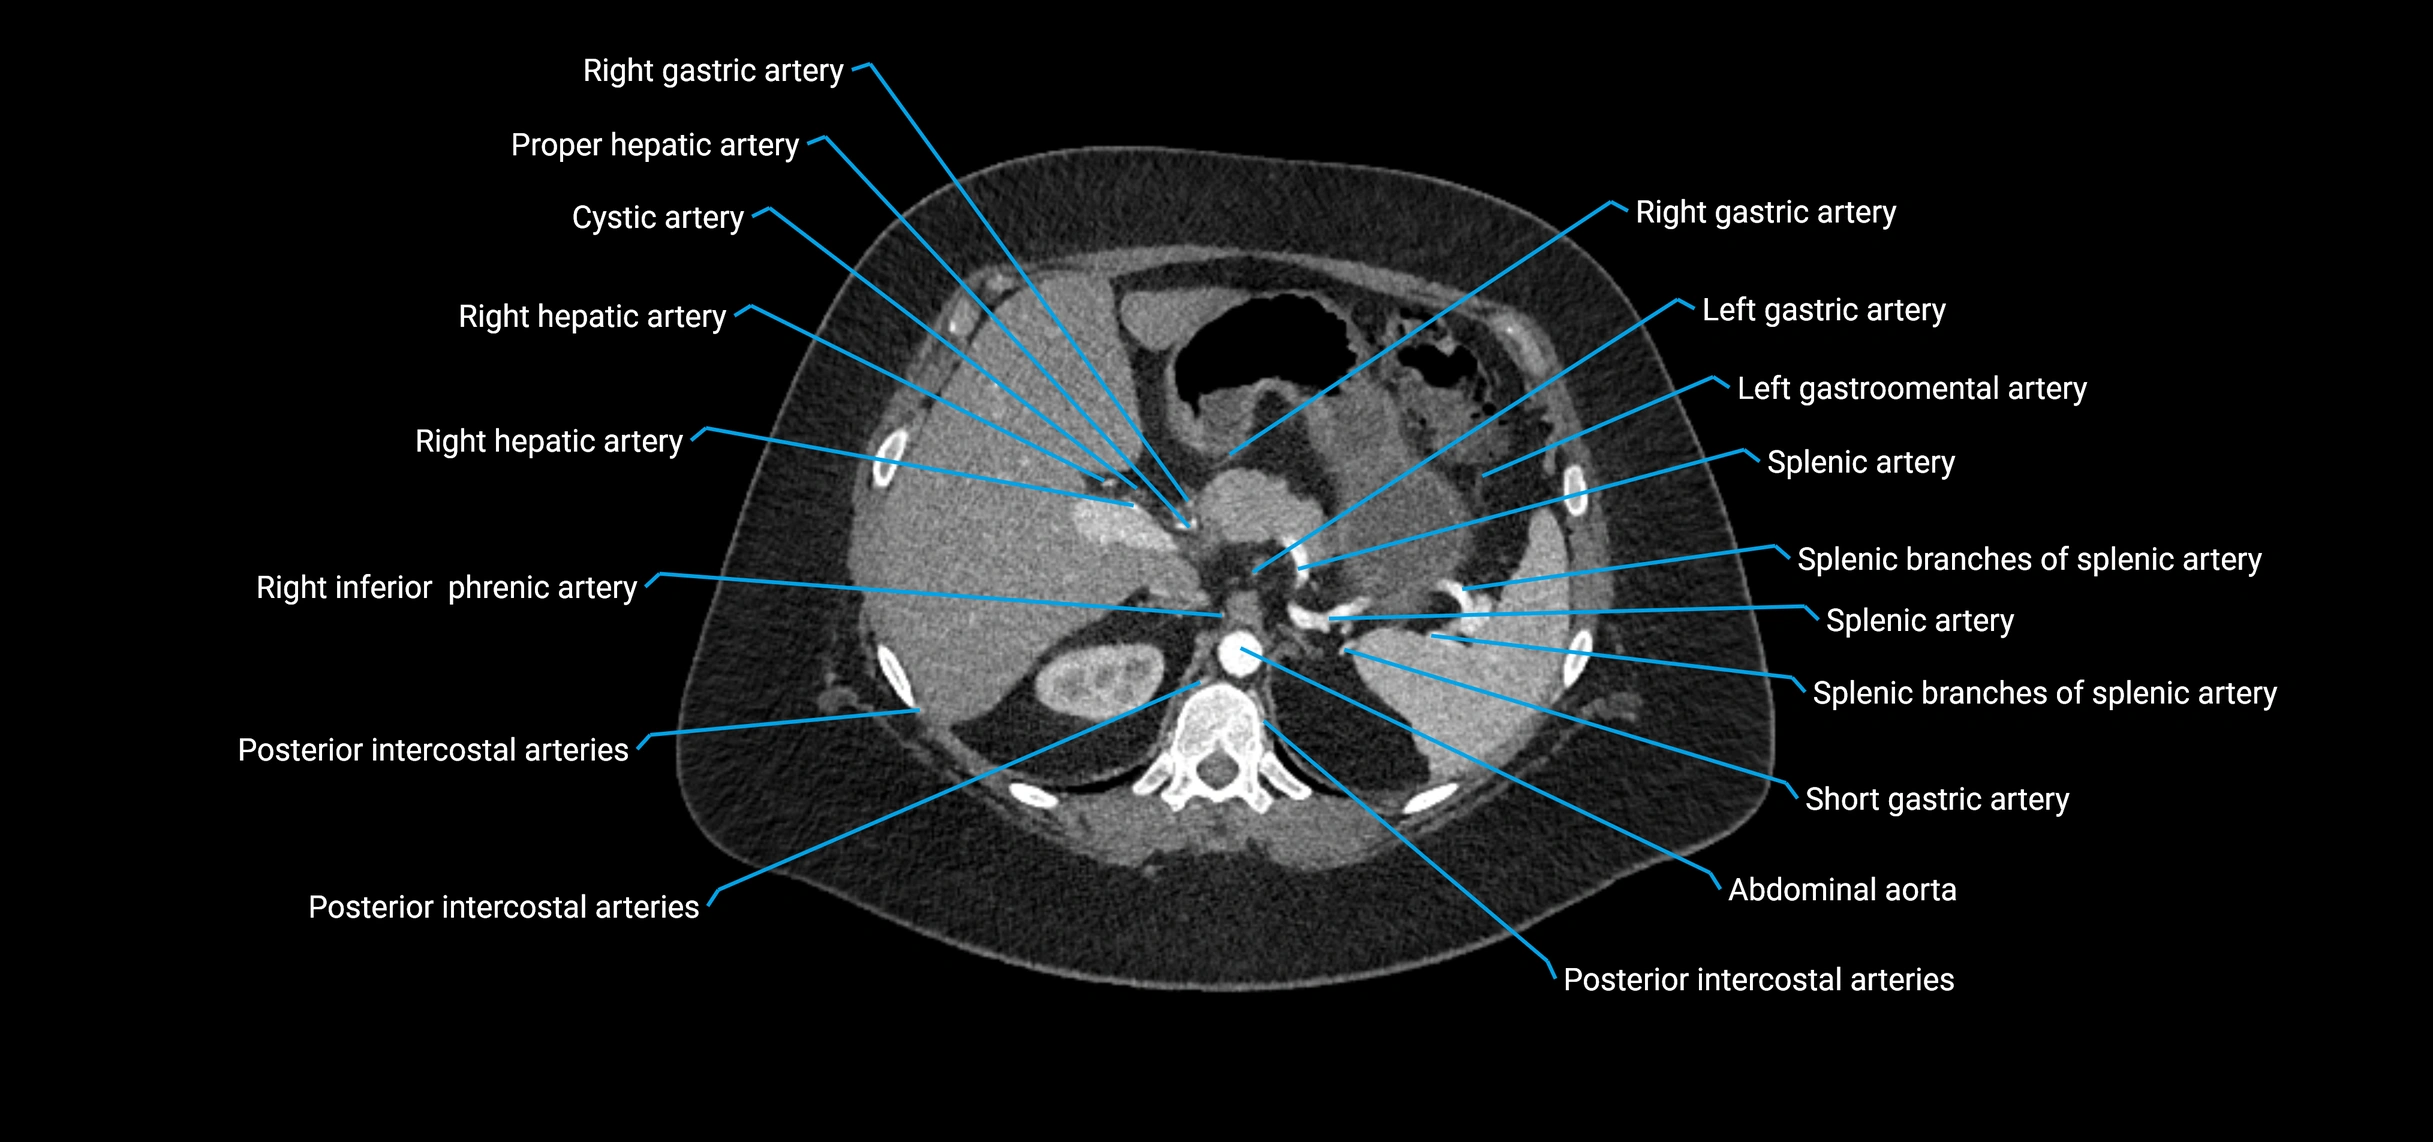

Contrast-enhanced CT (CTA):

• Gold standard for abdominal aortic imaging

• Provides excellent detail of lumen, wall, aneurysm, thrombus, and branch vessels

• Multiplanar and 3D reconstructions help in aneurysm measurement, stent graft planning, and dissection evaluation